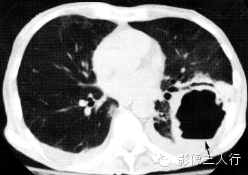

肺隔离症

(图2) |